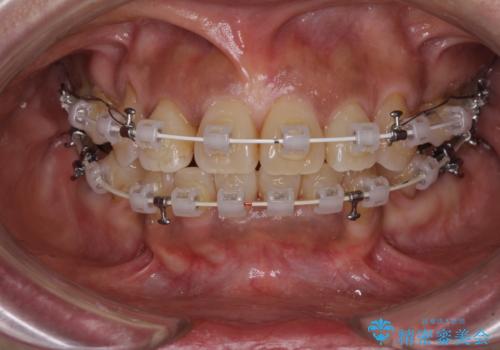

- 審美装置

- 2年4ヶ月

- 八重歯やクロスバイトを気にして来院された患者様です。

口元の突出感はありませんでしたが、デコボコが強く、非抜歯矯正とすると出っ歯仕上がりとなる可能性があったため、上下左右の第一小臼歯4本を抜歯し、ワイヤー装置にて矯正治療を行うこととしました。